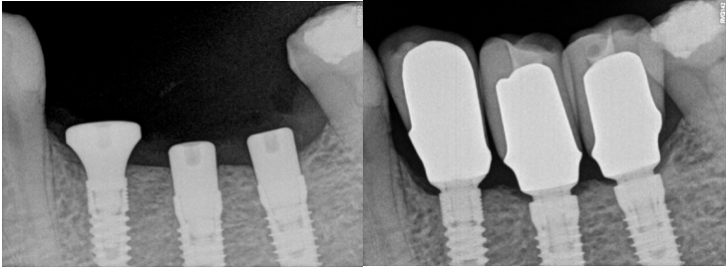

On the other hand, let’s admit, that all of us would choose Fig 1 A implant, without bone loss, and not Fig 1B implant, although the difference is very small. Sometimes clinicians tend to downplay this bone loss because simply they do not understand, why the bone is disappearing, and are not eager to learn.

Almost for one-decade platform switching was considered to be the most effective way to achieve this task. It was so effective that almost all implant companies have implemented platform switching as a “must be” feature of implant manufacturing.

Everybody made the conclusion that implant design was more important than the biology itself. However, recent clinical research of our group has shown that soft tissue thickness is an important factor in preserving crestal bone stability around implants.

Furthermore, it was clearly shown that even implants with platform switching modification couldn’t maintain bone if, at the time of implant placement, vertical soft tissues were thin.